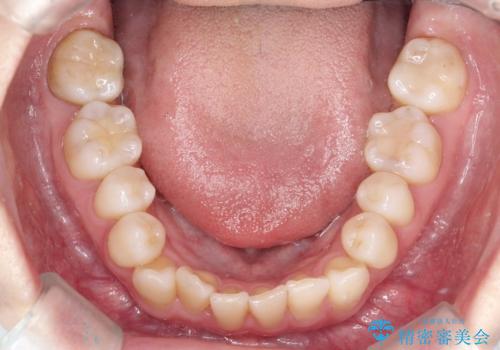

初診時の歯並びの状態としては、上下ともに前歯部中心としたの中等度のがたつき(叢生)があり、全特に左上の前歯は1本だけ引っ込んでおり、犬歯は外に飛び出した状態でした。

抜歯は行わず上顎の奥のスペースを利用して歯をスライドする方法の他に歯列弓の拡大やディスキング(歯と歯の間の隙間を作る処置)を行い叢生を改善しましています。